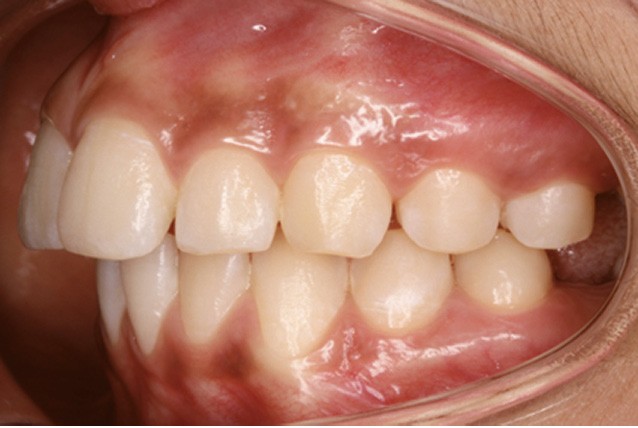

Examen endobuccal (fig. 2a-e)

L’hygiène est satisfaisante et le parodonte sain. On note aux deux arcades l’absence des premières molaires et la fermeture partielle des espaces d’extraction avec mésiorotation marquée de 17, 27 et 37. À la mandibule, l’encombrement antérieur est estimé à 2 mm et les espaces d’extraction résiduels à 12 mm.

Dans le sens transversal, malgré une occlusion correcte des secteurs latéraux, on observe une endoalvéolie maxillaire et une non-concordance des médianes incisives avec déviation de la médiane mandibulaire vers la droite. Le recouvrement incisif est normal.